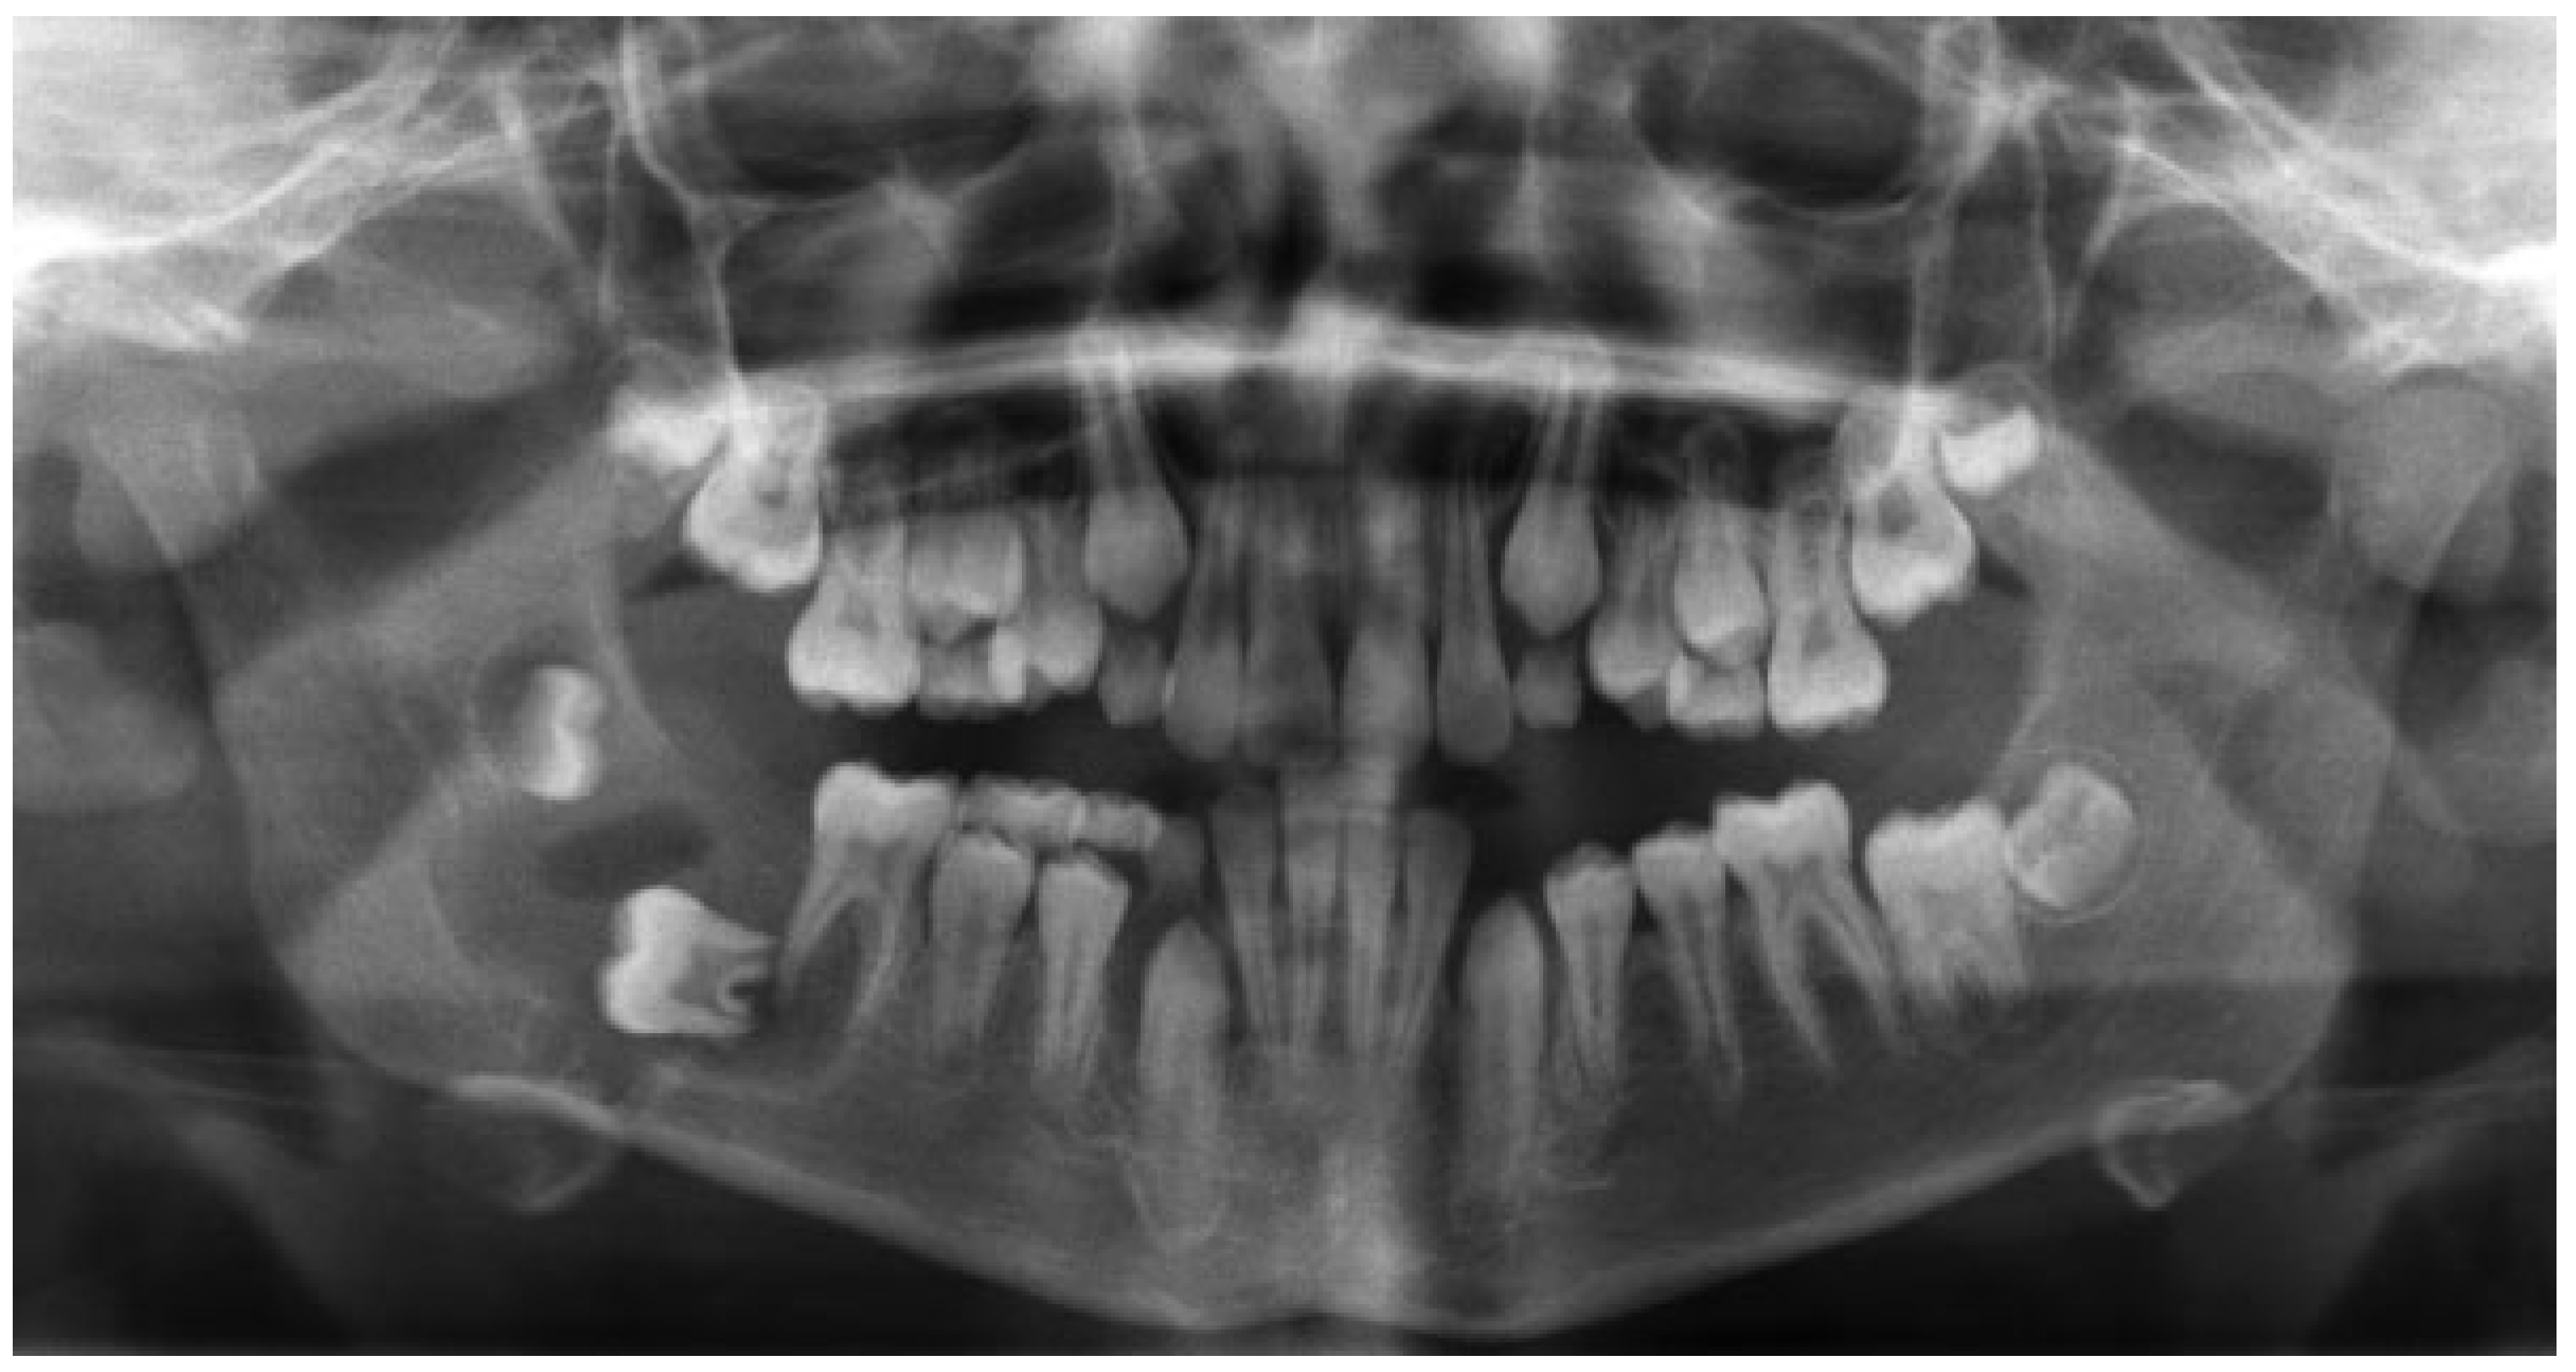

The third case was a 29-year-old white male with an expansile lesion of the anterior mandible. Panoramic radiograph showed a multilocular lesion involving the inferior border of the mandible and extending from the left second molar to the right canine (Figure 1). Incisional biopsy proved this lesion to be an ameloblastoma. The treatment plan included mandibular resection with 1-cm margin and immediate reconstruction with a free fibula microvascular flap. A tracheostomy for airway protection was also planned. A high-resolution CT scan was obtained followed by construction of a model. A custom prebent plate was obtained using the model as a reference. Using a combined transoral and transcutaneous approach, the mandible was resected from the left angle through the right second bicuspid. The 2.4-mm prebent reconstruction plate was placed (Figure 2). A free microvascular fibula flap with a skin pedicle was harvested. The fibula was contoured and adapted to the inner aspect of the custom-bent plate and secured with nonlocking screws (Figure 3). The skin pedicle was used to close the resulting soft tissue defect at the floor of the mouth. A tracheostomy was performed at the end of the case. The total surgical time including all the procedures was 10 hours and 33 minutes.

Figure 1. Panoramic radiograph showing large expansile multilocular radiolucent lesion. Case 3.